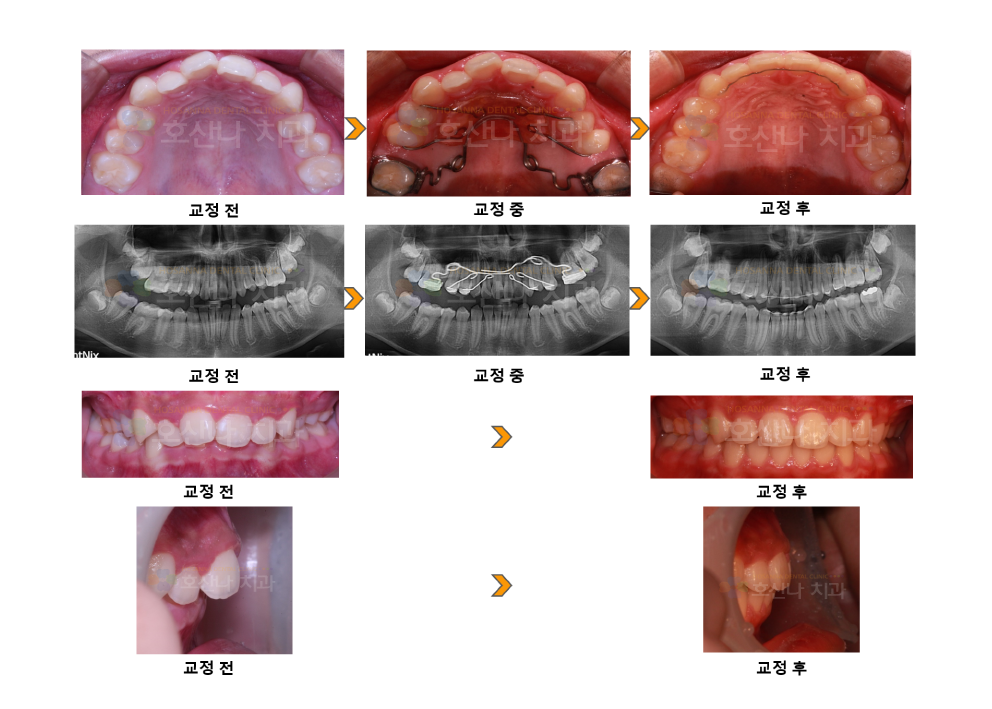

교정펜듈럼교정 시술 증례

< 펜듈럼교정 시술 증례 >

1. 치료대상

12y / male

2. 환자분 c.c

① 입이 안 들어갔으면 좋겠어요

② 가급적 이를 안 뽑고 싶어요

3. 진단결과

1) Skeletal CL II

2) Deep bite

3) U ant moderate crowding

4) Class II  molar relation

4. 교정 후 결과

2) Dental Rt. CL I Lt. CL I

3) straight profile

4) Overbite/Overjet normal

5. Dr.Koo Memo

최대한 발치 없이 교정을 진행하시고 싶어 하셔서

#16,26 의 펜듈럼 후방 견인을 통해 구치부 관계 개선 및 전치부 크라우딩 등을 모두 개선한 케이스입니다.

입술이 얇고 교정 전 정상 안모였기 때문에  안모를 유지하기 위해 최대한 비발치를 진행하였습니다.

펜듈럼 견인이 잘 진행 되었기 때문에 꽤 많은 양의 구치의 후방 이동이 필요하였음에도 좋은 결과를 얻었습니다.

6. 교정기간

2y 1m